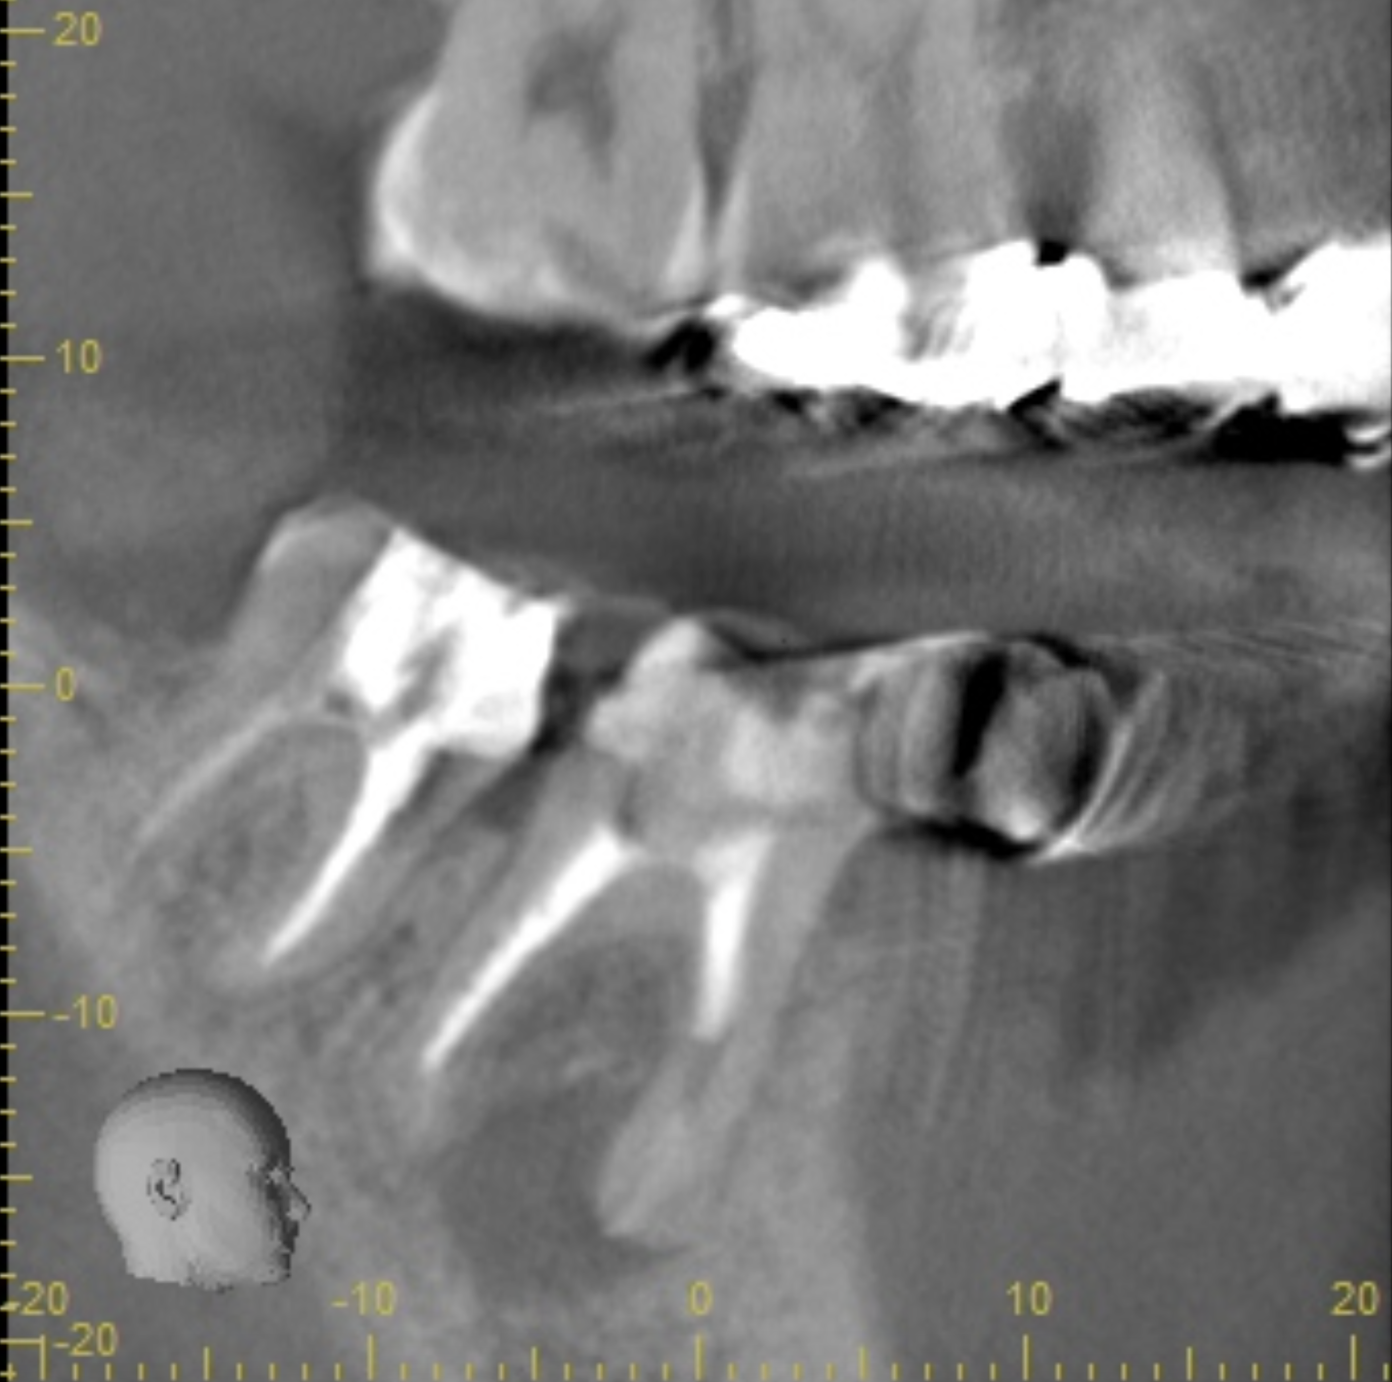

親知らずの抜歯 2019.07.17口腔外科の症例 親知らずの抜歯例です。CTにて接触が8mmあり、下唇の麻痺の可能性もありますが、手前の歯の当たっている部分が徐々に溶けてきています。抜歯後、手前の歯の揺れなども起こらず骨も回復してきています。費用:1万... 続きを読む